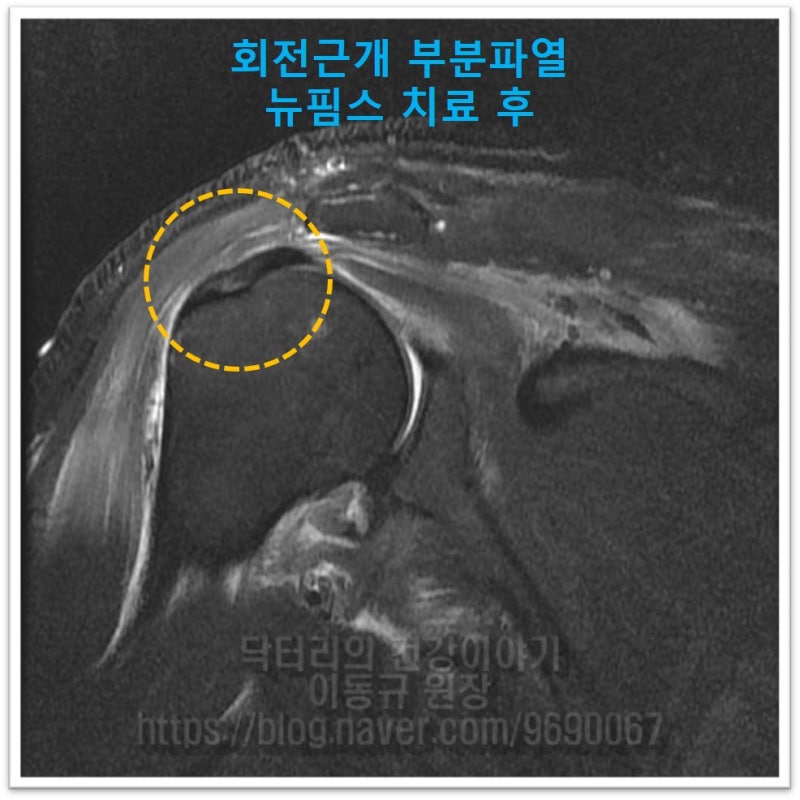

MRI 상 회전근개 힘줄의 상태가 매우 좋지 않으며 염증이 아주 심한 것으로 보입니다. 이에 대해 뉴핌스 치료를 시행하였습니다. 회전근개 질환에 대해 뉴핌스 치료는 힘줄 재생술을 통해 힘줄이 치유되어 건강해 지게 하는 추가적인 치료를 합니다.

회전근개 부분파열의 치료는 한번의 치료로 나을 수는 없습니다. 뉴핌스 치료 후 추가적인 힘줄강화 치료를 통해 5주간 환자를 치료하였습니다. 치료 후 결과를 보여드리면

치료 결과 MRI 에서 보이듯 회전근개 부분 파열에 대해서는 수술 없이 비수술적 치료로 회복될 수 있습니다. 단순 보전적 치료(약, 물리치료, 통증주사 등)로는 힘들 수 있다고 생각합니다. 뉴핌스 치료 처럼 조직을 치유시킬 수 있는 치료를 적극적으로 하는 것이 회전근개 질환이 진행되는 것을 피할 수 있고 회전근개가 건강해 질 수 있습니다. 회전근개 파열은 진행을 합니다. 대부분의 경우 퇴행성 변화로 인해 힘줄이 약해지면서 파열되기 때문입니다. '파열이 작을때', '파열이 부분파열일때' 초기에 적극적인 치료를 통해 더이상 진행되지 않게 해야합니다. 이미 파열이 커지거나 완전히 파열되면 수술적 치료를 해야하기 때문입니다.